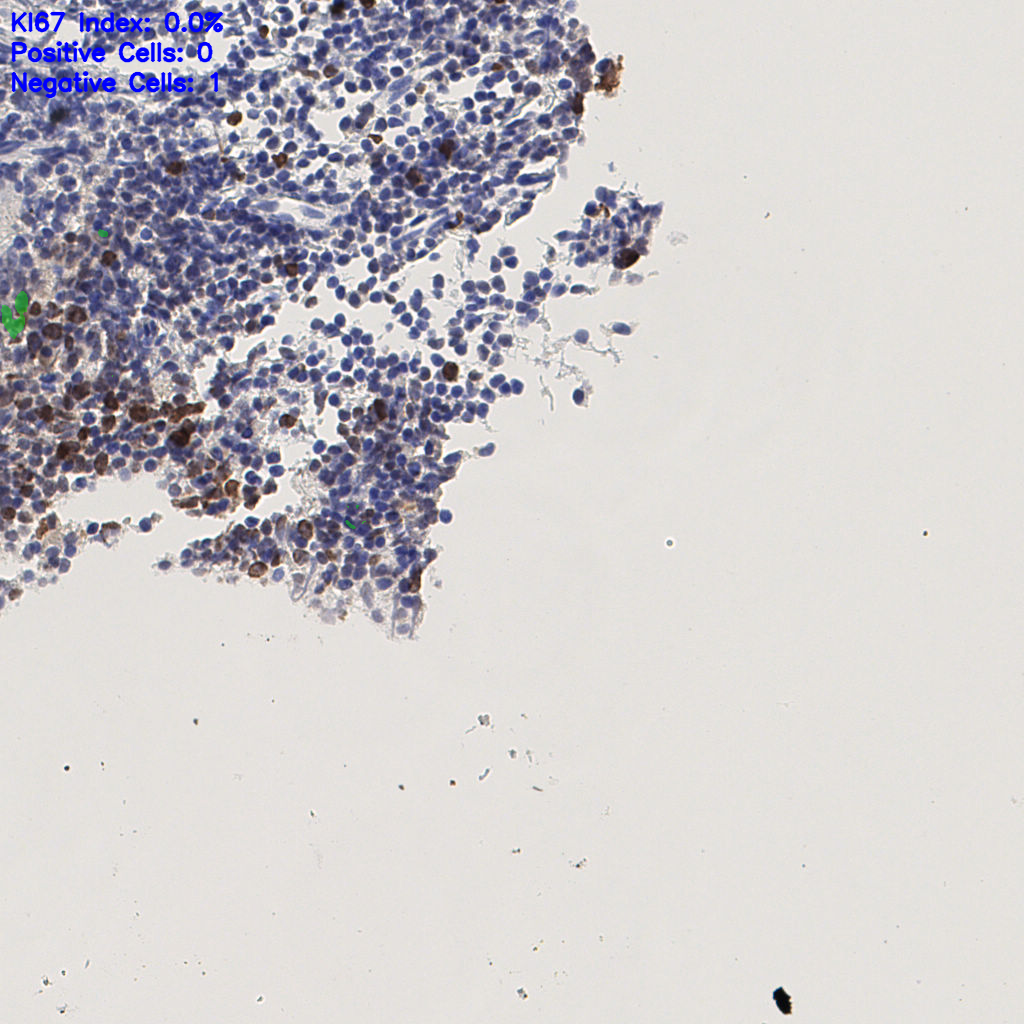

slice_61_10_x54656_y8960.png

slice_61_10_x5465...